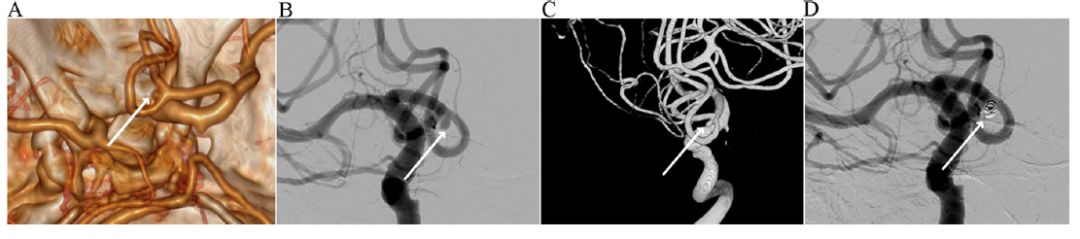

图2. 71岁男性患者,颅内有两枚小动脉瘤:1枚1.2mm动脉瘤位于左侧ACA的A2初始段(短箭头),另1枚2.3mm动脉瘤位于AcoA(长箭头)。常规VR图像(A)和立体VR图像清晰地描述这两枚动脉瘤;立体VR图像同时清晰地显示两个动脉瘤与中颅底骨质以及相邻血管分支的关系。常规DSA图像(B)最初无法清晰地显现1.2mm的小动脉瘤;而在3DRA图像(C)发现1.2mm动脉瘤(短箭头),阅片者再回顾阅读常规DSA图像时,辨认出1.2mm动脉瘤(短箭头)。常规DSA图像(D)可见血管内金属圈栓塞后的2.3mm动脉瘤(长箭头),1.2mm动脉瘤(短箭头)是在回顾读片时才辨认出。